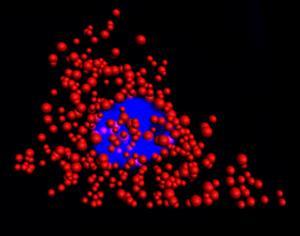

image: Quantum dots illuminate the locations of individual mRNA as red dots in the cytoplasm of a single HeLa cell. The blue region is the nucleus. This work was a collaborative effort between Illinois Bioengineering and Mayo Clinic researchers. view more

Quantum dots illuminate the locations of individual mRNA as red dots in the cytoplasm of a single HeLa cell. The blue region is the nucleus. This work was a collaborative effort between Illinois Bioengineering and Mayo Clinic researchers.

In experiments with HeLa cells and prostate cancer cells, the researchers found that dye-based FISH cell counts declined rapidly in minutes. The quantum dot-based FISH method provided long-term luminescence to allow counting of RNA for more than 10 minutes, making it possible to acquire 3D cell imaging.